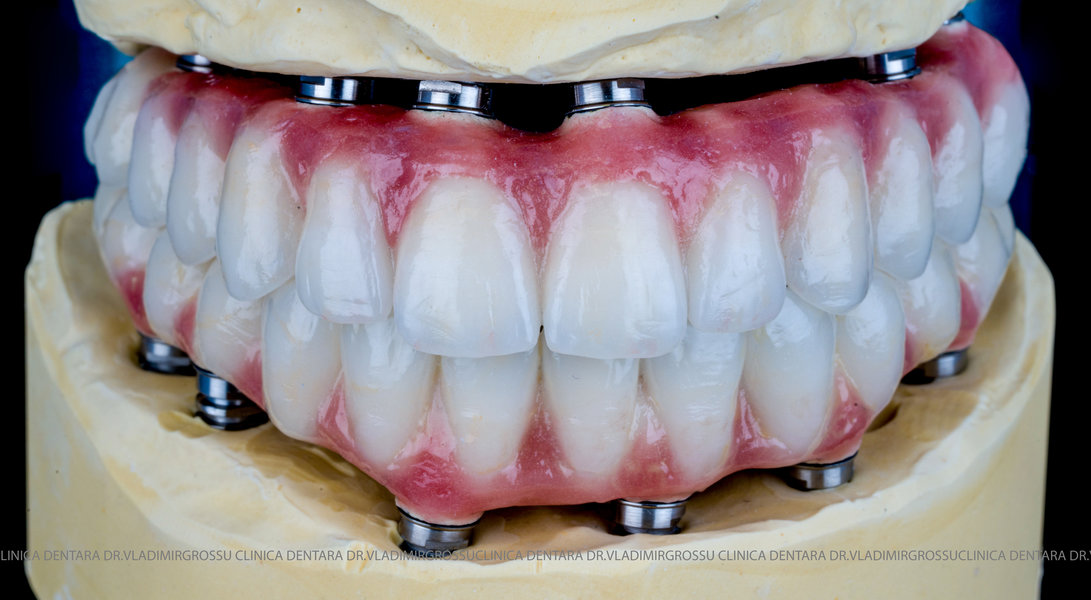

Cazuri clinice conceptul All-on-6